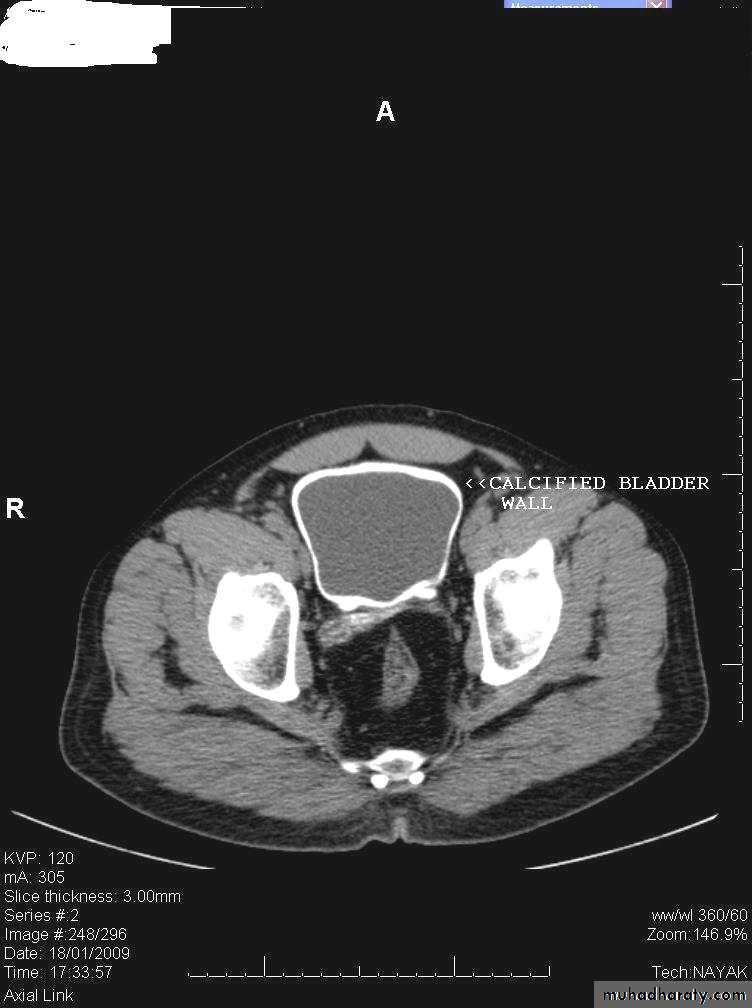

Calcification of the urinary bladder wall